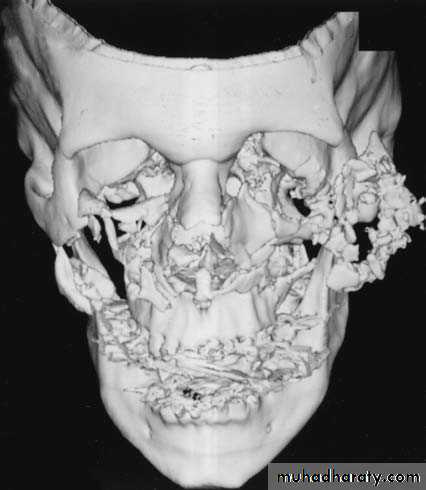

MAXILLOFACIAL GUNSHOT INJURIES

General features of maxillofacial ballistic injuries

Maxillofacial firearm-related injuries are customarily classified as either penetrating or perforating; each of these categories is determined by the terminal location of the projectile and its wounding effects.• Penetrating wounds are caused by missiles of low impact velocity, such as handgun bullets, with a small point of entry leading to the missile embedded in tissue.

• Perforating wounds are typically produced by higher velocity bullets, which create an exit wound that is often larger than the entrance.

• A third category is the avulsive or ablative injuries, characterized by significant bone and soft tissue loss. These are caused either by close-range shotgun blasts, with avulsion created by multiple pellets close to each other, or by high-velocity rifle bullets which may produce massive exit wounds as a result of bullet tumbling, bone fragmentation, or both.

Differences between gunshot and civilian injuries:

• The fractures are usually extensively comminuted.• Always compound and contaminated.

• The viability of bone fragments and the extent of dental injuries cannot be accurately evaluated preoperatively.

• Fracture treatment is complicated by soft tissue injury or loss.